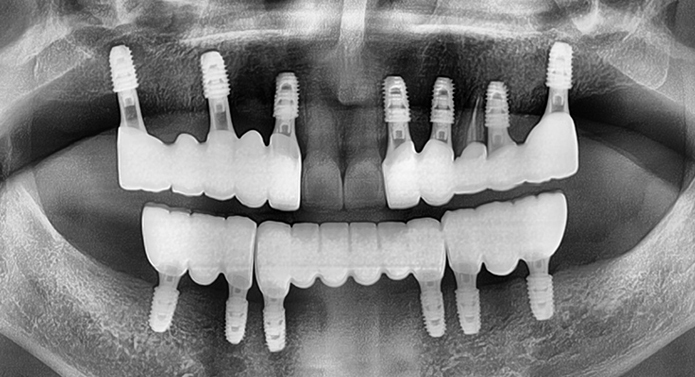

전체 임플란트는 상·하악 전체 치아가 상실되었을 때, 디지털 정밀 진단 → 최소한의 심기 → 고정형 보철 연결을 통해 자연 치아 기능과 심미성을 회복하는 디지털 기술력 기반의 치료입니다.

골 상태가 좋지 않아도 빠르게 고정되는 특수 나사 디자인

습기에 반응하는 초친수성 표면으로 골세포의 부착과 골유착을 획기적으로 향상

발치즉시, 즉시 부하, 뼈 질이 약한 고령환자까지 다양한 조건에서도 우수한 안정성 확보

전 세계 70개국 이상에서 사용되는 프리미엄 브랜드 SCI 논문 다수, 임상 연구로 효과 입증